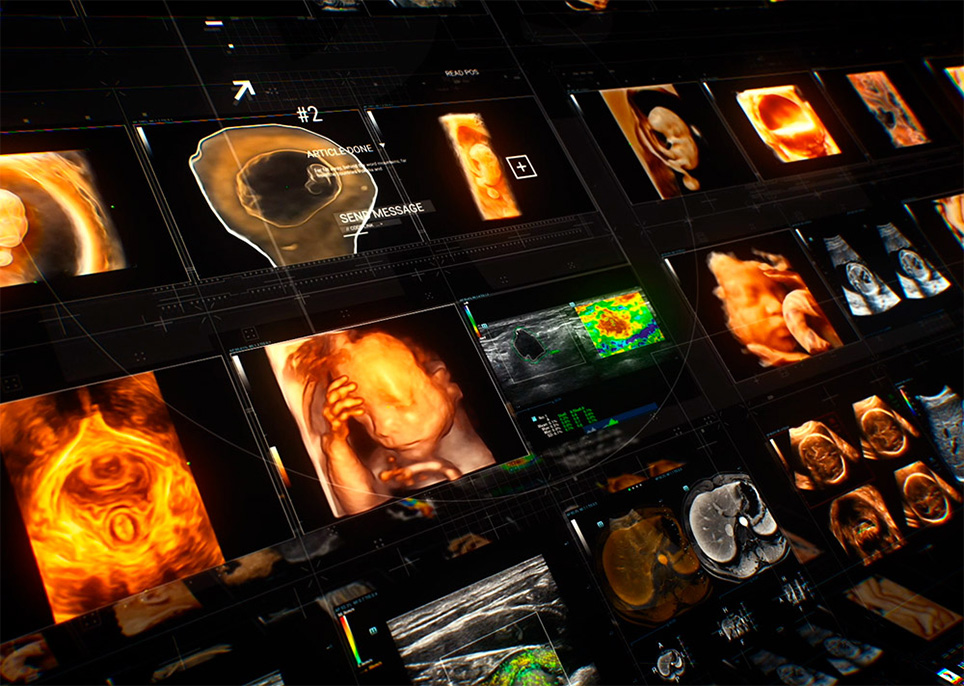

Avec l'Êvolution de la sociÊtÊ et les prÊoccupations croissantes concernant la santÊ des femmes, de plus en plus de femmes sont conscientes de l'importance des Êchographies rÊgulières en gynÊcologie obstÊtrique. La demande croissante d'examens Êchographiques a sans aucun doute lancÊ un nouveau dÊfi aux Êchographistes, sans compter que la demande est de plus en plus segmentÊe. Pour simplifier le processus et permettre à davantage de femmes de bÊnÊficier de services de diagnostic par Êchographie de grande qualitÊ, Mindray s'engage à innover et propose une gamme complète de solutions intelligentes pour les soins de santÊ des femmes et des enfants, gr?ce à Zone Intelligence?. Nous espÊrons doter les Êchographistes d'une ??arme magique?? leur permettant de rÊpondre à de nombreux scÊnarios d'examen, avant la grossesse, en cours de grossesse, pendant le rÊtablissement post-partum et chez le nouveau-nÊ, pour protÊger davantage leur santÊ.

Une gamme complète de solutions intelligentes pour les soins de santÊ des femmes et des enfants gr?ce à Zone Intelligence?